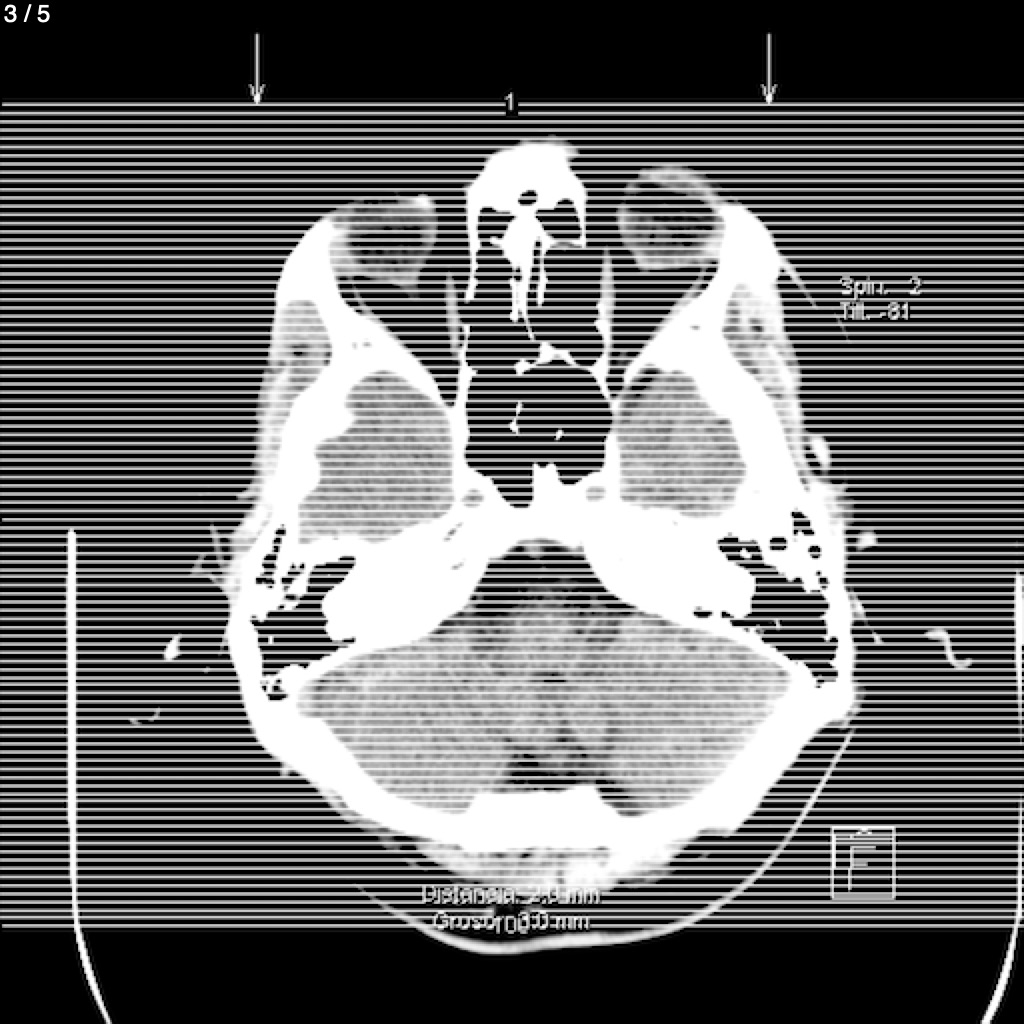

Rufino Eduardo Tovar Lopez - Cabeza Simple_Craneo (Adulto)